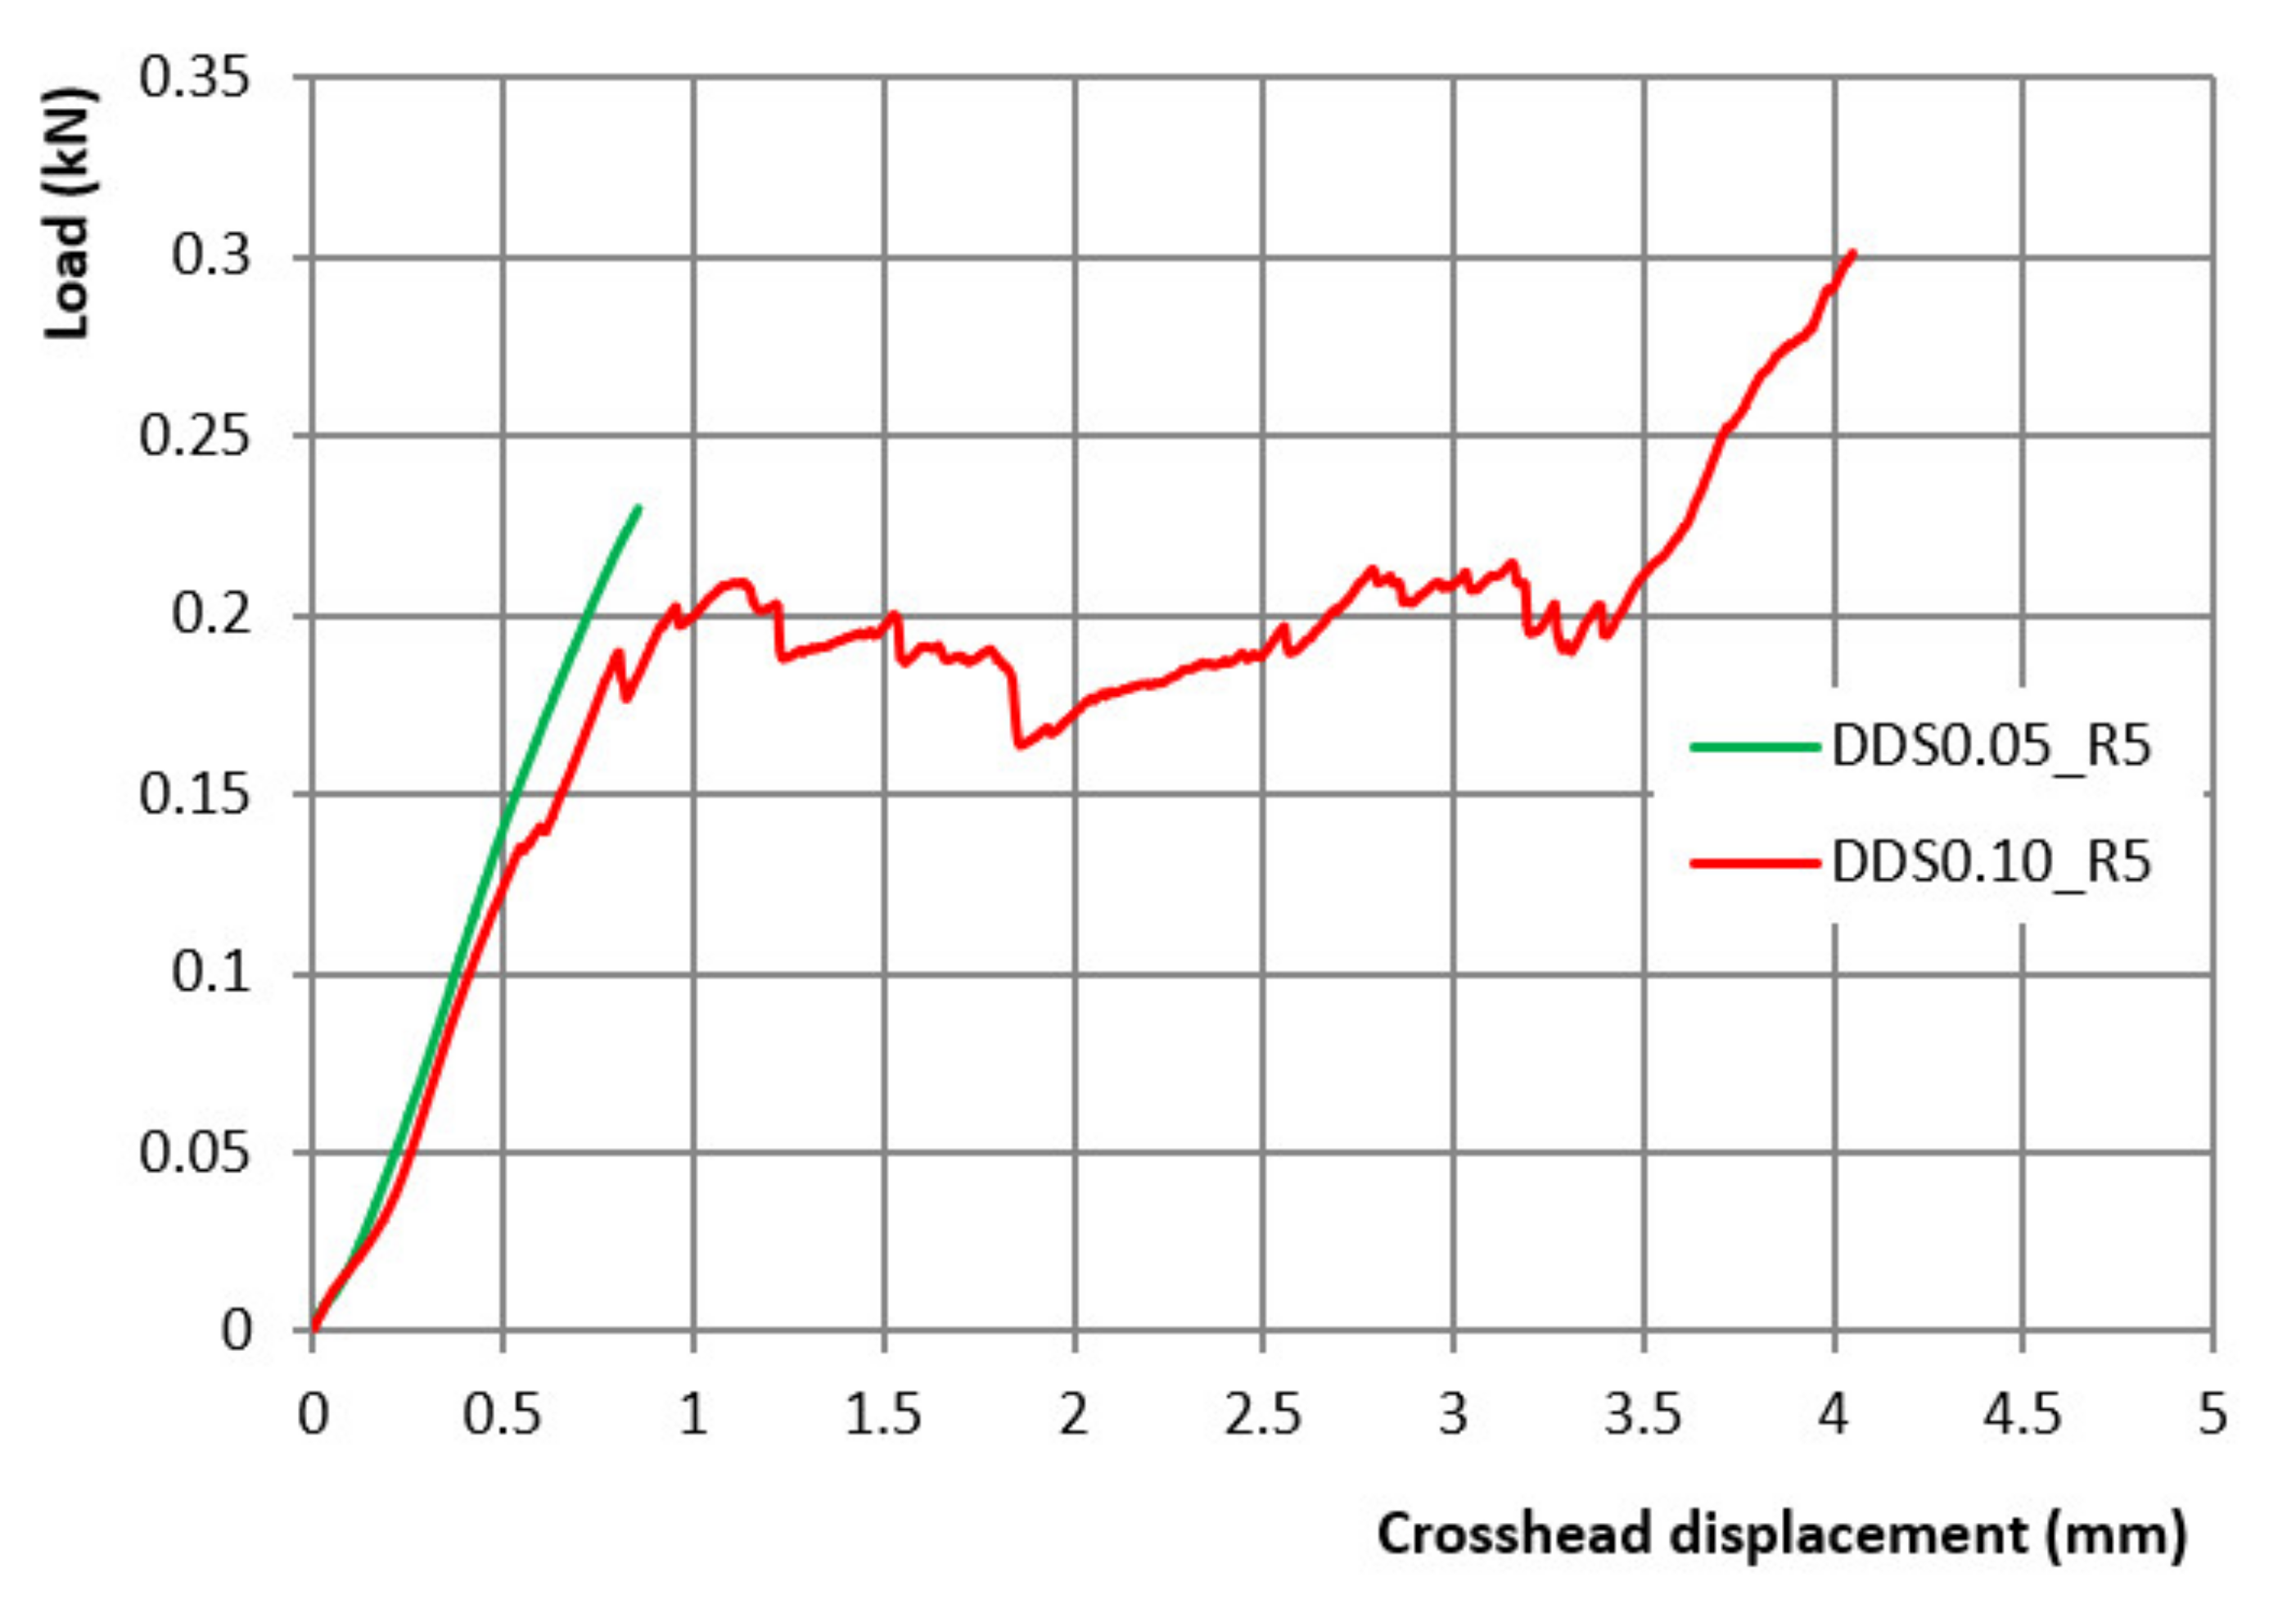

2.7. DDS Mechanical Strength

4.2.9. DDS Mechanical Strength